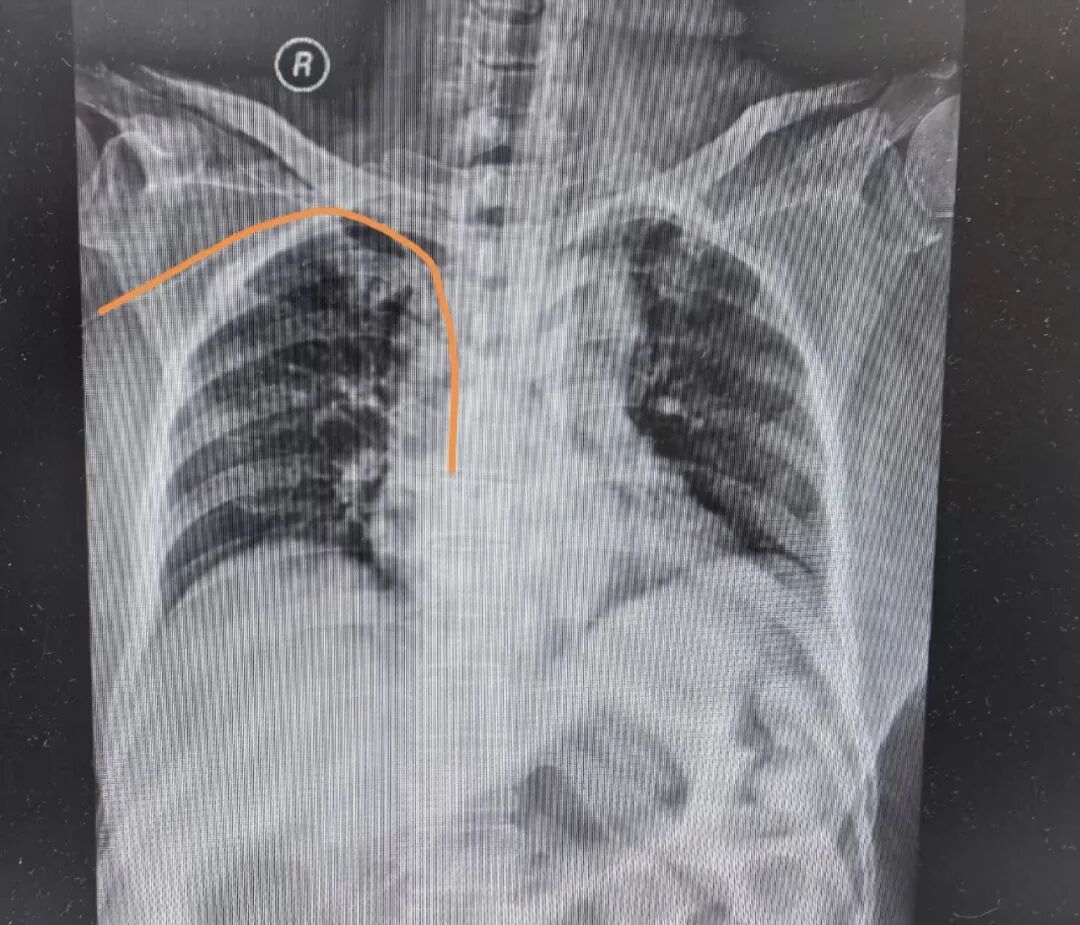

入院后,内科十一(肿瘤科一)护理单元护士长袁月第一时间发现了患者及家属的焦虑情绪。深知首诊患者信任来之不易的她,结合患者病情,迅速制定针对性解决方案,决定采用PICC心腔内电图定位技术为患者进行导管复位。该技术是我院肿瘤科2024年引入的临床新技术,相较于传统定位方式,具有实时精准、无需反复影像学检查、避免辐射暴露等显著优势,能有效解决导管异位难题,提升治疗安全性与效率。

操作中,护理团队成员凭借精湛的专业技艺,精准捕捉心腔内电图波形的每一处变化,实时调整导管位置,全程规范操作、严谨细致。在PICC心腔内电图定位技术的支持下,整个复位过程无需反复进行影像学检查,不仅省去了患者漫长的等待时间,更避免了额外的辐射暴露,仅用数十分钟,异位的PICC导管便成功复位,精准抵达指定位置。